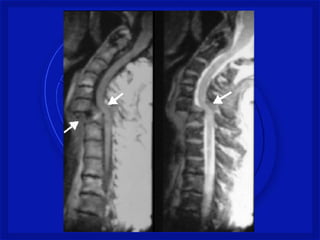

•Lesão Traumática da

raqui(coluna) e medula espinal

resultando algum grau de

comprometimento temporário ou

permanente das funções

neurológicas

ASIA – American Spinal Injury Association

TRM – Traumatismo Raqui-

Medular